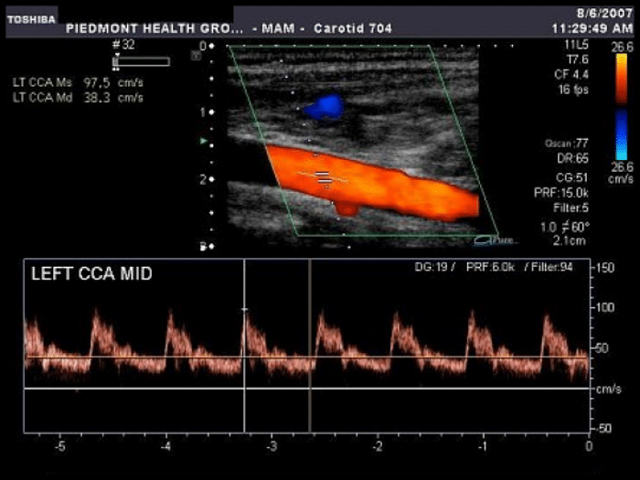

- рентгенографию позвонков шеи;

- МРТ сосудов головы.

Чтобы установить скорость течения крови, выявит тромбы или бляшки потребуется дуплексное сканирование. МРТ или КТ, которые проведут с применением контрастного вещества, дадут большое количество ценой информации о состоянии пациента. Данных исследований будет достаточно, чтобы поставить точный диагноз и назначить адекватное и эффективное лечение.